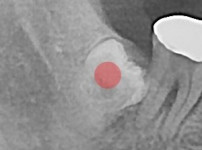

완전 매복 사랑니